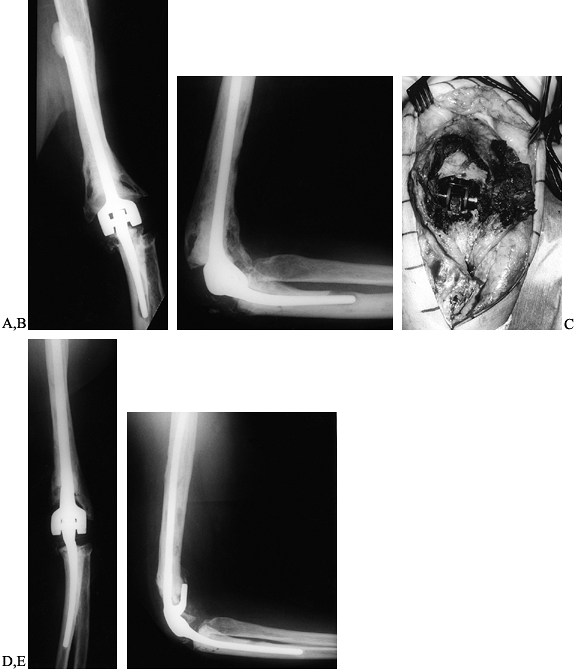

presents as an acute fracture due to cortical thinning from osteolysis (Fig. 102.19).

development of extensive bone loss (Fig. 102.20).

Figure 102.19. A:

AP radiograph of a well-functioning Morrey-Coonrad total elbow arthroplasty 4 years following the index procedure for posttraumatic arthritis. B: Note the osteolysis evident at the tip of the ulnar component. C: AP radiograph following a pathologic fracture of the ulna at the site of the aforementioned osteolysis 1 year later. D: Lateral radiograph. E: AP radiograph following a revision of the ulnar component. Note the cement leakage evident at the tip of the ulnar component through a cortical perforation. F: Lateral radiograph. |

Figure 102.20. A:

AP radiograph of a 67-year-old woman 10 years after revision total elbow arthroplasty for posttraumatic arthritis. The patient has mild aching pain in the elbow that is worse following activities. Cement leakage is evident at the tip of the humeral component. B: Lateral radiograph. Note the radiolucency around the ulnar component and the osteolysis evident at the tip. C: Intraoperative photograph of titanium synovitis from a loose total elbow arthroplasty. D: AP radiograph following revision to a long-stem cemented Morrey-Coonrad total elbow arthroplasty. This gave the patient complete pain relief and return of function. E: Lateral radiograph demonstrating autogenous bone graft behind the flange of the humeral component. |